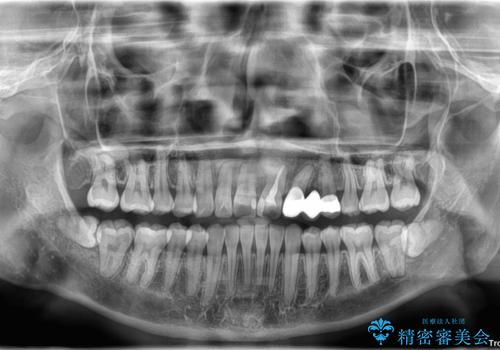

- 上下の前歯のデコボコを改善したいと来院された患者様です。

上顎の歯列幅が狭く、それによって歯が並ぶスペースが不足しています。

また下顎の歯列幅も制限され、内側に歯が倒れています。

それらを改善するため上顎に拡大装置を用いて、審美装置にてワイヤー矯正を行いました。